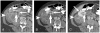

Materials and methods: We identified CT scans of 20 patients (13 women and 7 men; mean age, 63 years) with either perirenal liposarcoma (n = 11) proven at histopathology or large exophytic angiomyolipomas (n = 9) determined by 2-year stability (n = 6) or histopathology (n = 3). Two independent readers unaware of the final diagnoses recorded the presence of the following CT findings: (1) tumoral vessel extending into the renal cortex, (2) tumoral vessel extending into the renal hilum, (3) renal parenchymal defect at the site of tumor contact, (4) intratumoral hemorrhage, (5) nonfat attenuating intratumoral nodules, and (6) calcification.

Results: A tumoral vessel extending into the renal cortex was seen only in angiomyolipomas (7 and 6 of 9 patients versus 0 and 0 of 11 liposarcomas for readers 1 and 2, respectively; P < 0.005 for both). A parenchymal defect was more commonly seen in angiomyolipomas (7 and 6 of 9 angiomyolipomas versus 1 and 1 of 11 liposarcomas for readers 1 and 2, respectively; P < 0.05 for both). Calcifications were seen by both readers in 6 of 11 liposarcomas but not in any angiomyolipomas (P < 0.05). The other recorded findings were not useful in distinguishing CT features (P > 0.1 for both readers).

Conclusions: In the evaluation of a fatty perinephric mass at CT, the presence of a tumoral vessel extending into the renal cortex or a renal parenchymal defect at the site of tumor contact strongly favors the diagnosis of exophytic angiomyolipoma, whereas calcifications suggest liposarcoma.